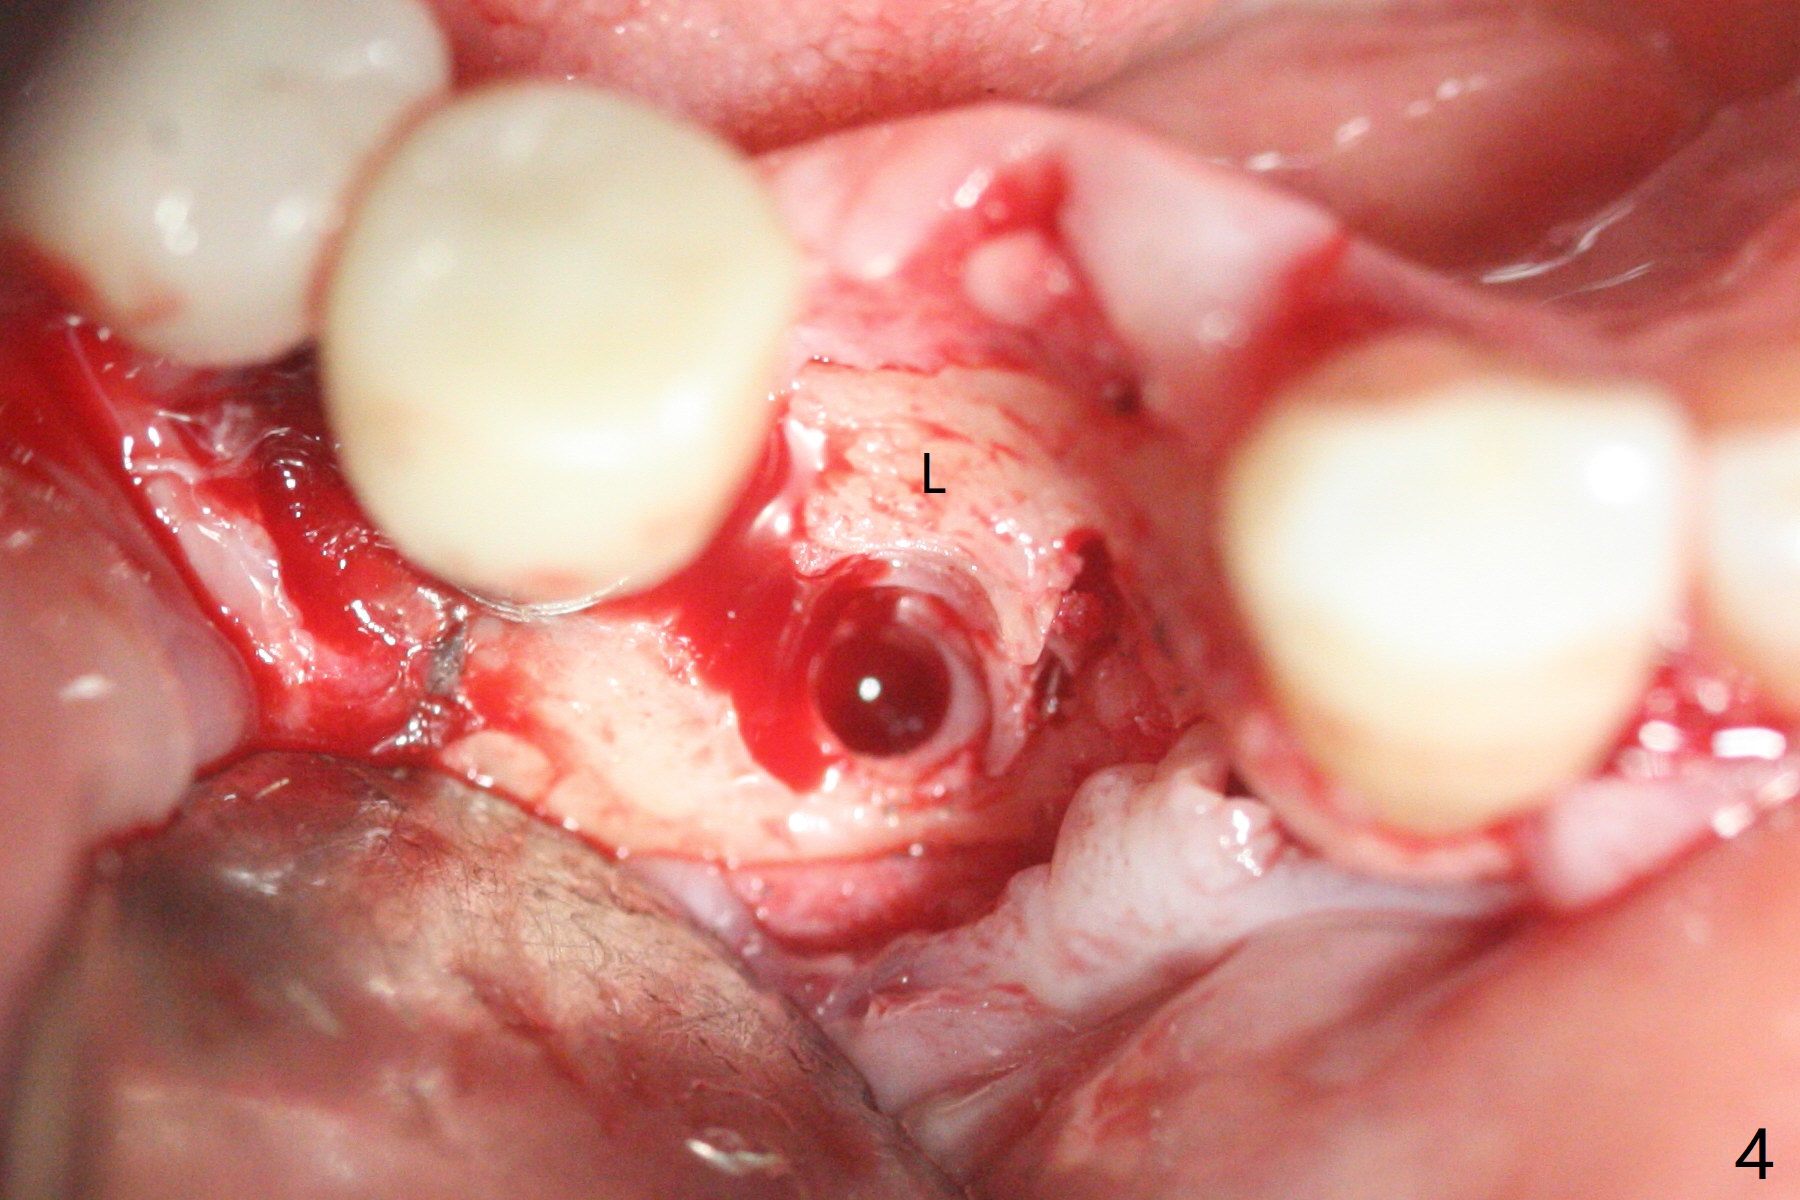

61岁女右下4(粘固后5.5年)植体周围炎(颊侧牙龈没有角化龈(图一:*)),因为颊侧种植(图二),翻瓣证实(图三),取出4.5毫米两段式植体,在舌侧骨质(图四:L)即刻植入2.5毫米一段式植体(图五),颊侧缺损植入大量粘性骨粉(图六:*),覆盖PRF膜后,缝合(图七),与图二对比,窄植体明显舌侧移位。术后一个月撤除牙周敷料(图八),并没有马上制作临时牙冠,让病人容易搞好局部卫生,促进伤口愈合(图九),术后三个月塞入龈线(图十:^),制备基台,植体在牙槽嵴中性位置(颊舌侧),但愿颊侧有足够再生骨质,覆盖植体螺纹。